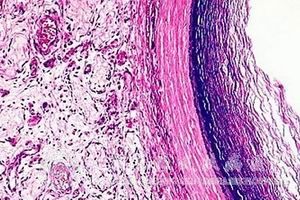

通过显微镜观察可以发现,表皮囊肿的瘤壁是由两层不同组织构成的,其中外层是比较薄的纤维结缔组织,内层则为复层的鳞状上皮,上皮层是面向囊腔的,其表面会有许多的角化*,经过不断的脱落就成了囊的内容物质,并使肿物不断增大。

在囊肿周围的蛛网膜组织会呈现纤维增生与玻璃样变,有时还可出现异位巨噬*,周围的淋巴*与组织*呈浸润性生长。囊内的物质具有一定的组织毒性,当这些物质溢出并到达蛛网膜的下腔则可导致肉芽样炎症的发生,另外,靠近囊的脑组织可能会发生胶质增生。